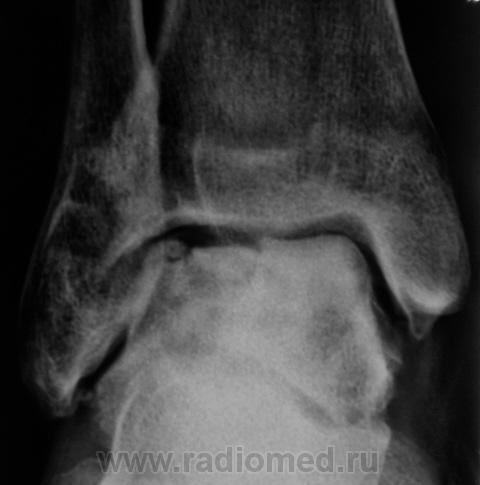

А присутствует линейный (или лентовидный, я их путаю) остеопороз, а это признак острого процесса.

Только не последнее...

+ за лентовидный остеопроз...

С учётом стрелочек, надо полагать, остеомиелит!..

Будем думать, что некроз блока таранной кости не такой уж и асептический, какая-то инхвекция там есть.

Посттравматический артроз с кистовидной перестройкойлатерального мыщелка Субхондральное уплотнение исужение суст. щелей естьИ неконгруэнтность большеберцового эпифиза к таранной маленько просматривается?